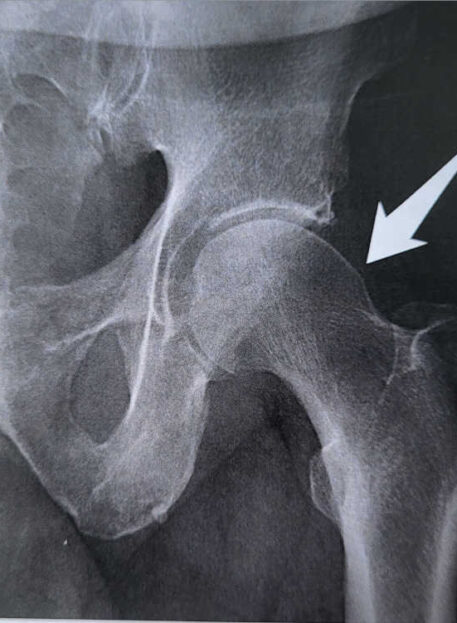

Utesnitveni sindrom kolčnega SKLEPA

01. Vrste utesnitvenega sindroma kolka

- CAM tip – nepravilna oblika glavice stegnenice.

- PINCER tip – nepravilna oblika ponvice (acetabuluma).

- Kombinirani tip – prisotna oba vzroka hkrati.